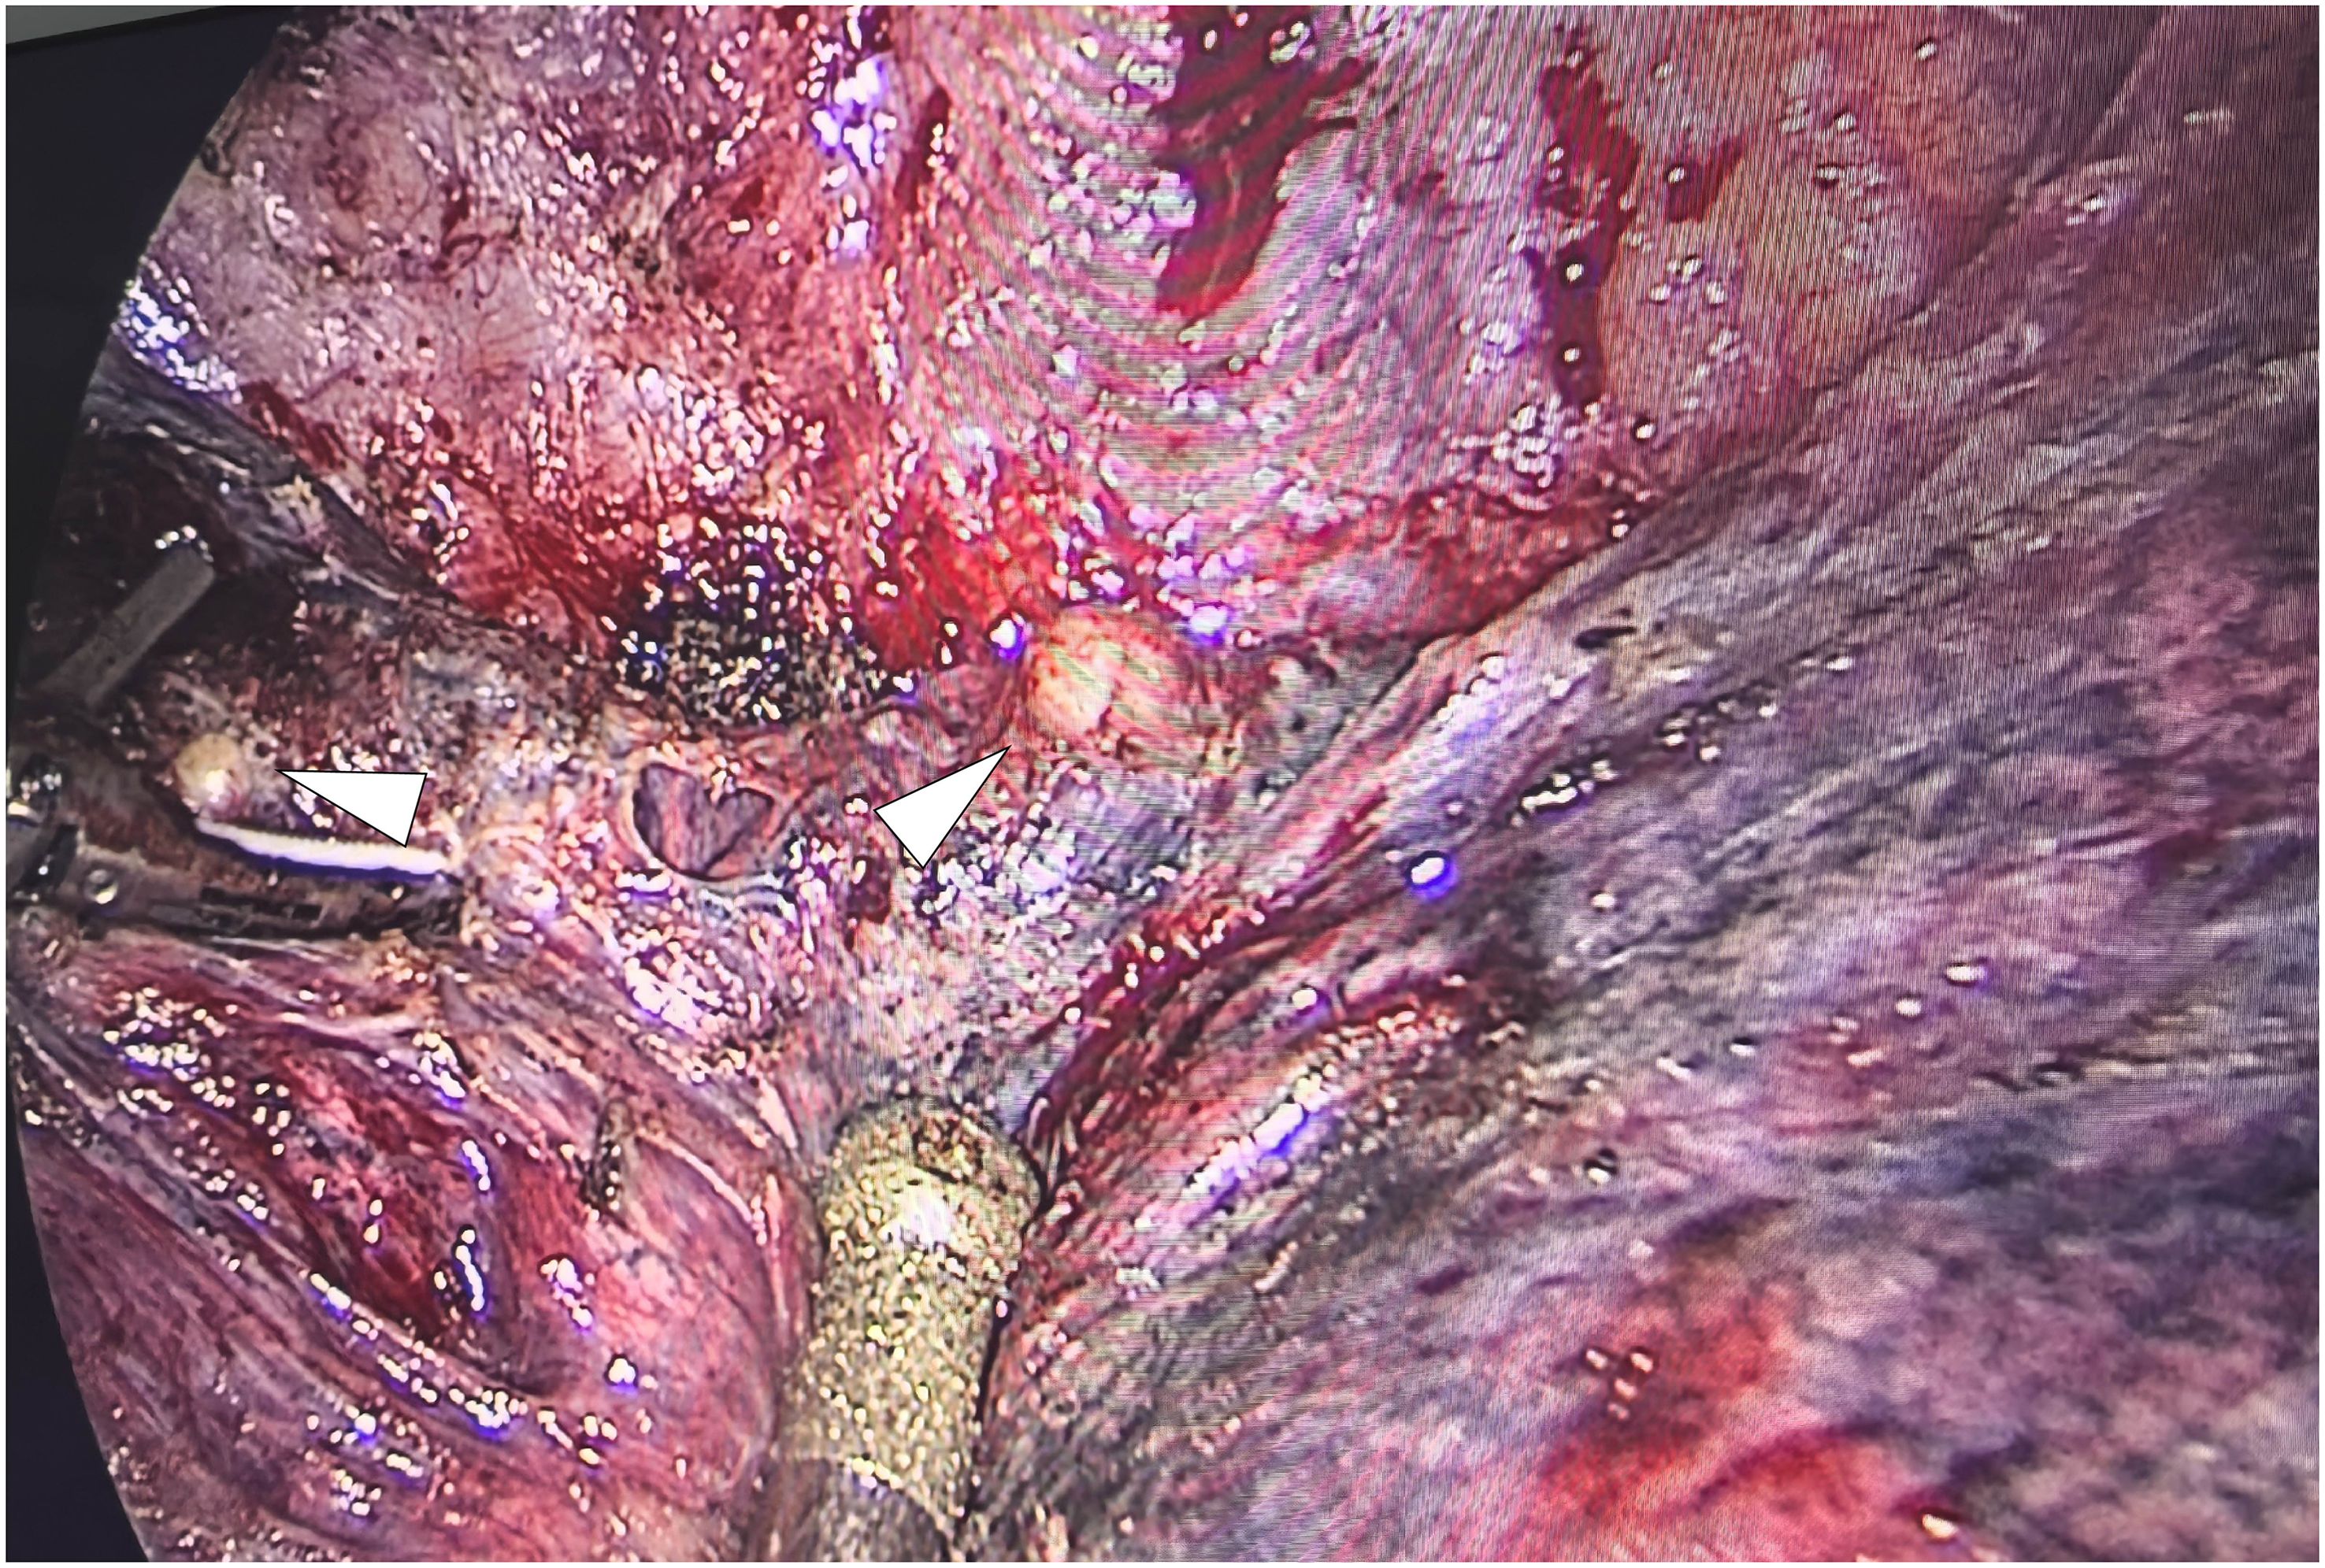

Abstract: This article presents a case study of a patient with early-stage lung cancer who received comprehensive management at our institution throughout the entire clinical course. During follow-up, multiple progressively enlarging solid nodules were detected in the right lung and pleural cavity. Positron emission tomography-computed tomography (PET-CT) demonstrated increased fluorodeoxyglucose (FDG) uptake in these nodules, with a maximum standardized uptake value (SUVmax) of 3.568. Following a multidisciplinary team (MDT) discussion, surgical resection of the nodules was undertaken. Pathological examination confirmed the diagnosis of necrotizing sarcoid granulomatosis (NSG), with special staining and microbiological testing yielding negative results, thereby excluding infectious lesions and tumor metastasis. This case highlights the critical importance of distinguishing metastatic tumors from NSG when new intrapulmonary or pleural nodules appear post-lung cancer surgery. Surgical biopsy is demonstrated to be an effective modality for achieving a definitive diagnosis.